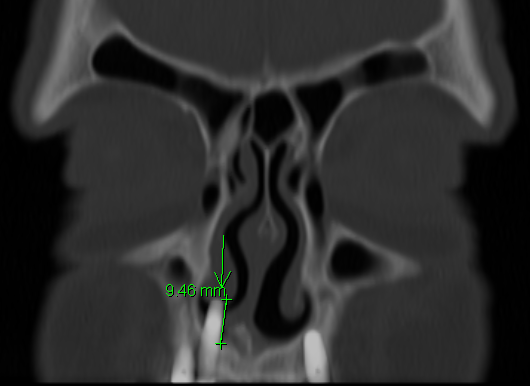

| A yellow discharge is associated with the object. A coronal CT image demonstrates extrusion of a dental implant 9.5mm into the right nasal cavity. |

|

Additional implants extruding into the maxillary sinuses without radiographic disease.